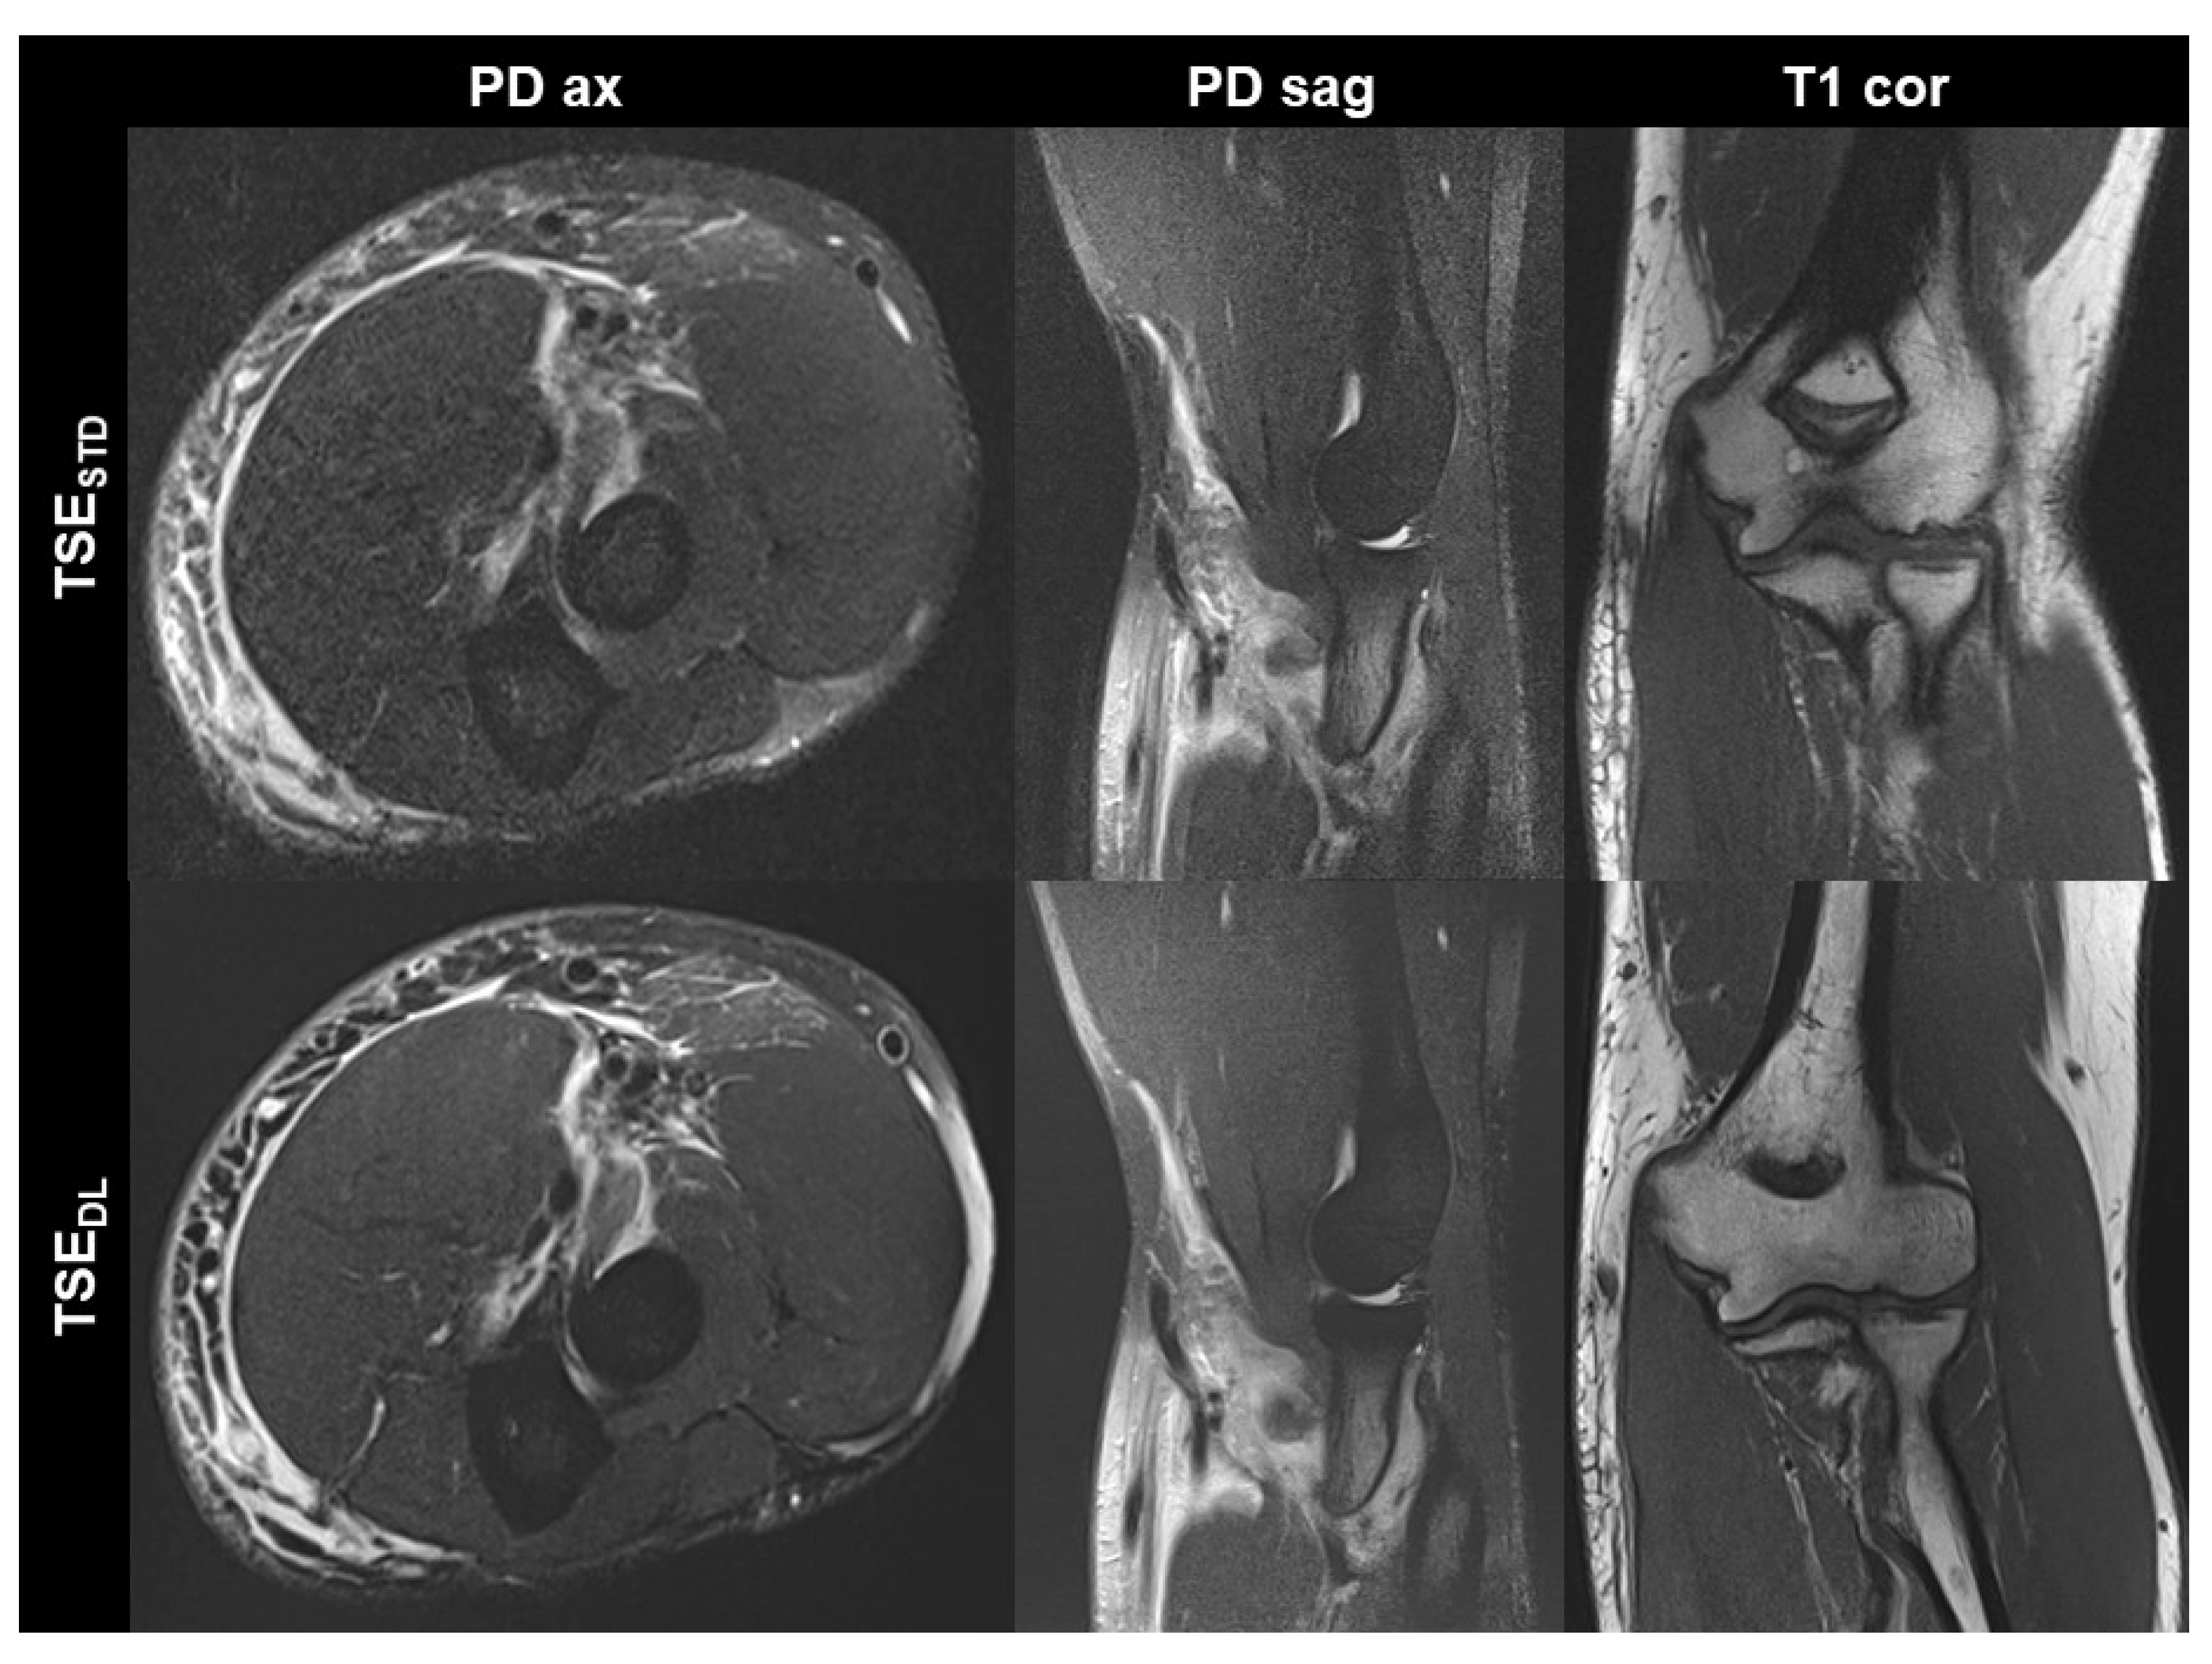

Figure 2. Non-contrast elbow MRI acquired at 3 T in a 70-year-old male patient with the institution’s standard turbo spin echo (TSE) sequences (TSESTD, upper row) and deep learning-reconstructed TSE sequences (TSEDL, lower row). In this example the standard and DL-reconstructed images show very similar image quality. In the TSEDL images, all anatomic details are well depicted, showing that the reduced acquisition time did not lead to a loss in detail. Additionally, edge sharpness in the coronal T1-weighted images (T1 cor) is slightly increased in the TSEDL image.